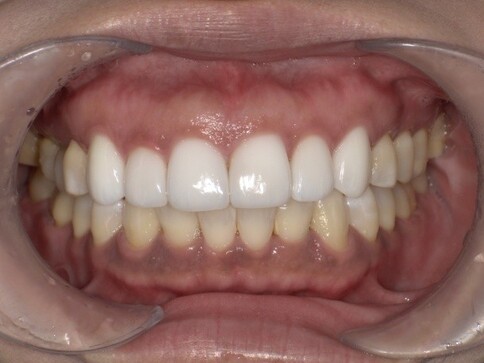

✨ 三、 四至六顆:微笑曲線重塑

Case 7:外突內收打造理想笑線,提亮色階。

Case 8:拆除舊連排假牙,換成獨立顆數全瓷冠。